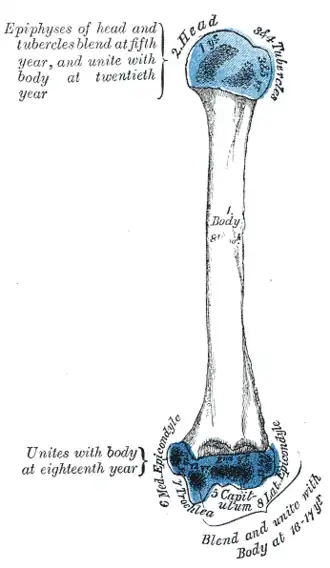

Plan of ossification of the humerus. (Medial epicondyle labeled at lower left.) | |

Left humerus. Anterior view.

Left humerus. Anterior view. -